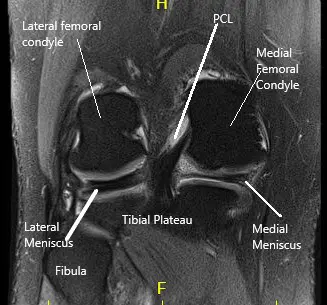

La resonancia magnética de la rodilla derecha sugirió una gran ruptura en forma de mango de cubo del menisco medial, desplazada hacia la muesca intercondilar y sobre el cuerno anterior.

Resonancia magnética de la rodilla derecha en la sección sagital y coronal.